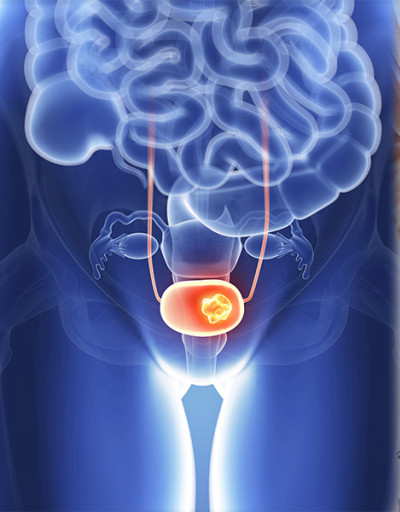

전립선암 초기증상 전립선암 발병 위험이 높은 남자나이나 일정 연령 이상의 남자는 특히나 더 조심해야 하고 항상 신경 써야 해요. 전립선암은 남자의 생식기관에 위치한 작은 샘인 전립선에 발생하는 암의 일종인데요. 전립선은 정자에 영양을 공급하고 지켜주는 체액을 생산하고 분비하는 할 일을 해요. 전립선암은 전립선의 비정상 세포가 성장하고 통제할 수 없이 증식해서 종양을 형성할 때 발생해요.

전립선암은 느리게 성장할 수 있으며 초기 단계에서는 무증상인 그럴 경우가 많아요. 그러나 암이 자라서 전립선을 넘어 전이된다면 배뇨 곤란, 소변 또는 정액의 혈액, 뼈 고통 및 피로와 같은 심각한 고통을 일으킬 수 있어요.